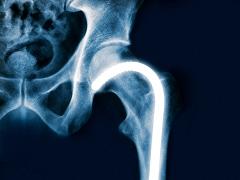

Osteoporose Lees meer over Osteoporose Osteoporose

Osteoporose is een aandoening van het skelet met een verhoogd risico op fracturen. Deze fracturen hebben een groot effect op morbiditeit, mortaliteit en kwaliteit van leven. Osteoporose wordt vaak pas laat ontdekt. Verreweg de meeste osteoporosepatiënten hebben de diagnose pas na een (eerste) fractuur gekregen. Daarna wordt de beschikbare behandeling in veel gevallen niet optimaal toegepast of opgevolgd. Doordat er bij psychiatrische patiënten vaak sprake is van verschillende risicofactoren, kan zorg op maat alleen geboden worden na een goede inventarisatie hiervan. GGZ-verpleegkundigen kunnen een signalerende functie vervullen bij hun patiënten als het om deze risicofactoren gaat. Denk aan onvoldoende vitamine D, gebrek aan lichaamsbeweging roken, en alcoholgebruik maar ook aan een laag lichaamsgewicht, hoog valrisico en een lage calciuminname. Ook is het belangrijk de aandoeningen en de specifieke medicatie te kennen waarbij er sprake kan zijn van een verhoogd risico op osteoporose of fracturen. Voorkomen is beter dan breken!